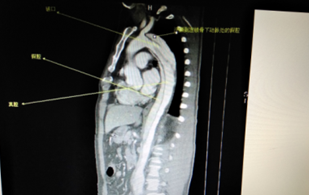

術(shù)前CT檢查(顯示為主動(dòng)脈夾層)